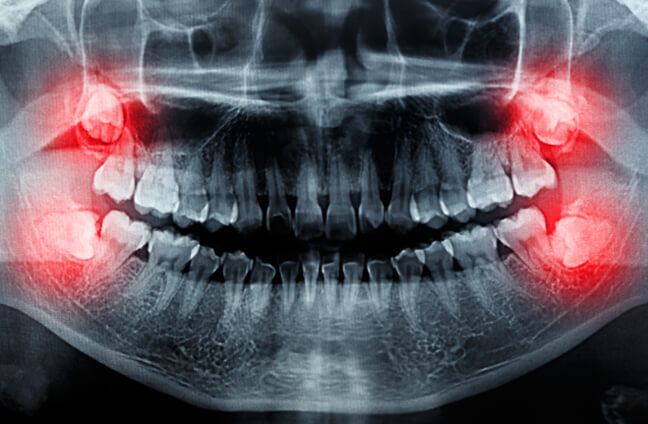

Our mouths can’t handle wisdom teeth due to a lack of space, leading to impaction. Wisdom teeth can develop sideways and damage surrounding teeth if they do not have enough room to grow. Tooth impaction and crowding can be excruciatingly painful. When this appears on X-rays, wisdom tooth extraction is recommended. Our dentists can assist you with this sort of extraction.